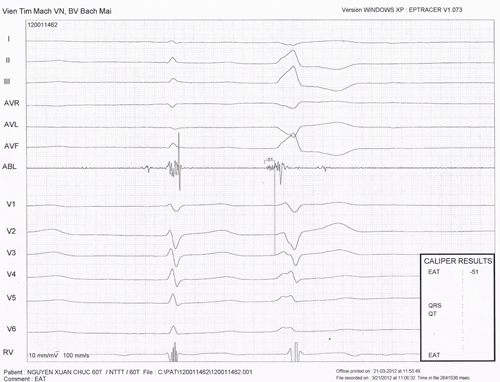

Hình 5: Điện tâm đồ bề mặt của hội chứng WPW điển hình với đường dẫn truyền phụ ở vùng trước vách bên phải.

Hình 6: Cơn tim nhanh vào lại nhĩ thất (AVRT). Ở chuyển đạo V1 nhìn rõ sóng P dẫn truyền ngược đi sau phức bộ QRS với RP